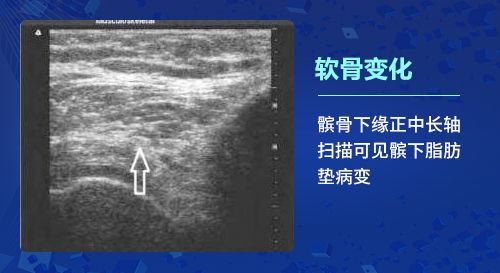

一、软骨变化:

骨关节炎的基本病理改变是软骨变性,出现软骨细胞纤维化、骨质增生及滑膜炎等改变。肌骨超声检查能够发现骨关节炎患者最初始的软骨改变,在软骨的厚度基本上没有发生实质性变化的时候就可以发现软骨透声模糊、边缘毛糙等细微的变化;利用高分辨率能力,检查软骨完整性(毛糙、变钝、分布不均)及厚度、软骨透声的清晰程度以及软骨表面的轮廓光滑度的变化,甚至出现局限性变薄或消失,以此很好的反映骨关节炎各个阶段的病理变化。